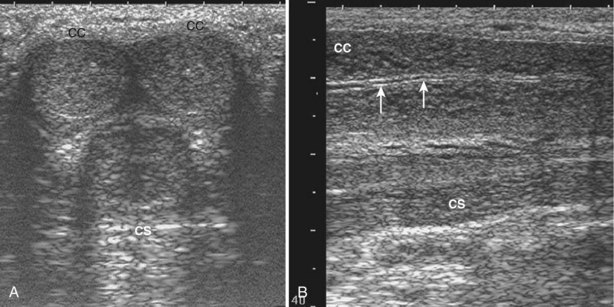

An edging artifact occurs when sound waves strike a curved surface or interface at an incident angle, resulting in refraction of the wave along the plane of the interface (Fig. 4–23).

Figure 4–23 When sound waves strike a surface or interface at a “critical angle,” the wave is refracted without significant reflection.

An incident wave at this angle (the critical angle) will not be directly reflected to the transducer, resulting in a hypoechoic “shadow.” This artifact is commonly seen in testicular ultrasonography and transrectal ultrasonography (Fig. 4–24). It can be overcome by changing the angle of insonation.

Figure 4–24 A, The curved surface of the tunica albuginea of the upper pole of testis creates a critical angle edging artifact (arrows). B, The rounded surfaces of the lateral lobes of the prostate as they meet in the prostatic urethra create an edging artifact (arrows) in this transverse image of the prostate.